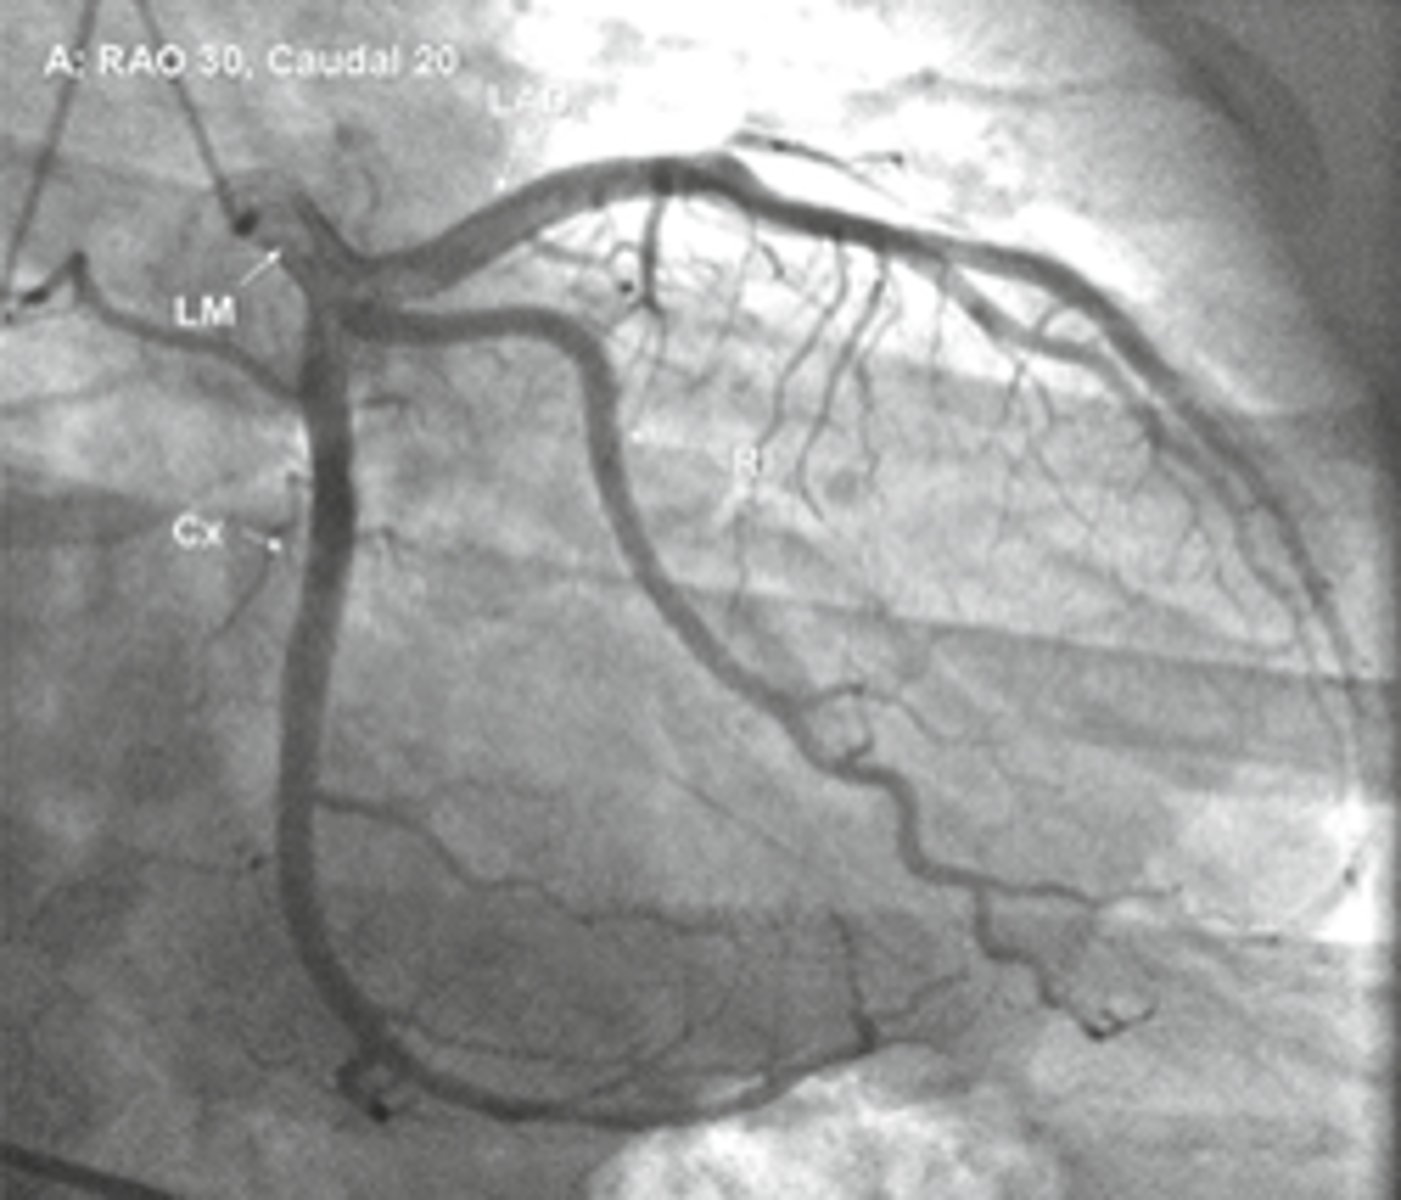

RAO

Cx is in front, what view

caudal

spine is seen on bottom left or right, what view

rao caudal

view

lao caudal

whats the spider shot

LAD

in LAO caudal what vessel is on top